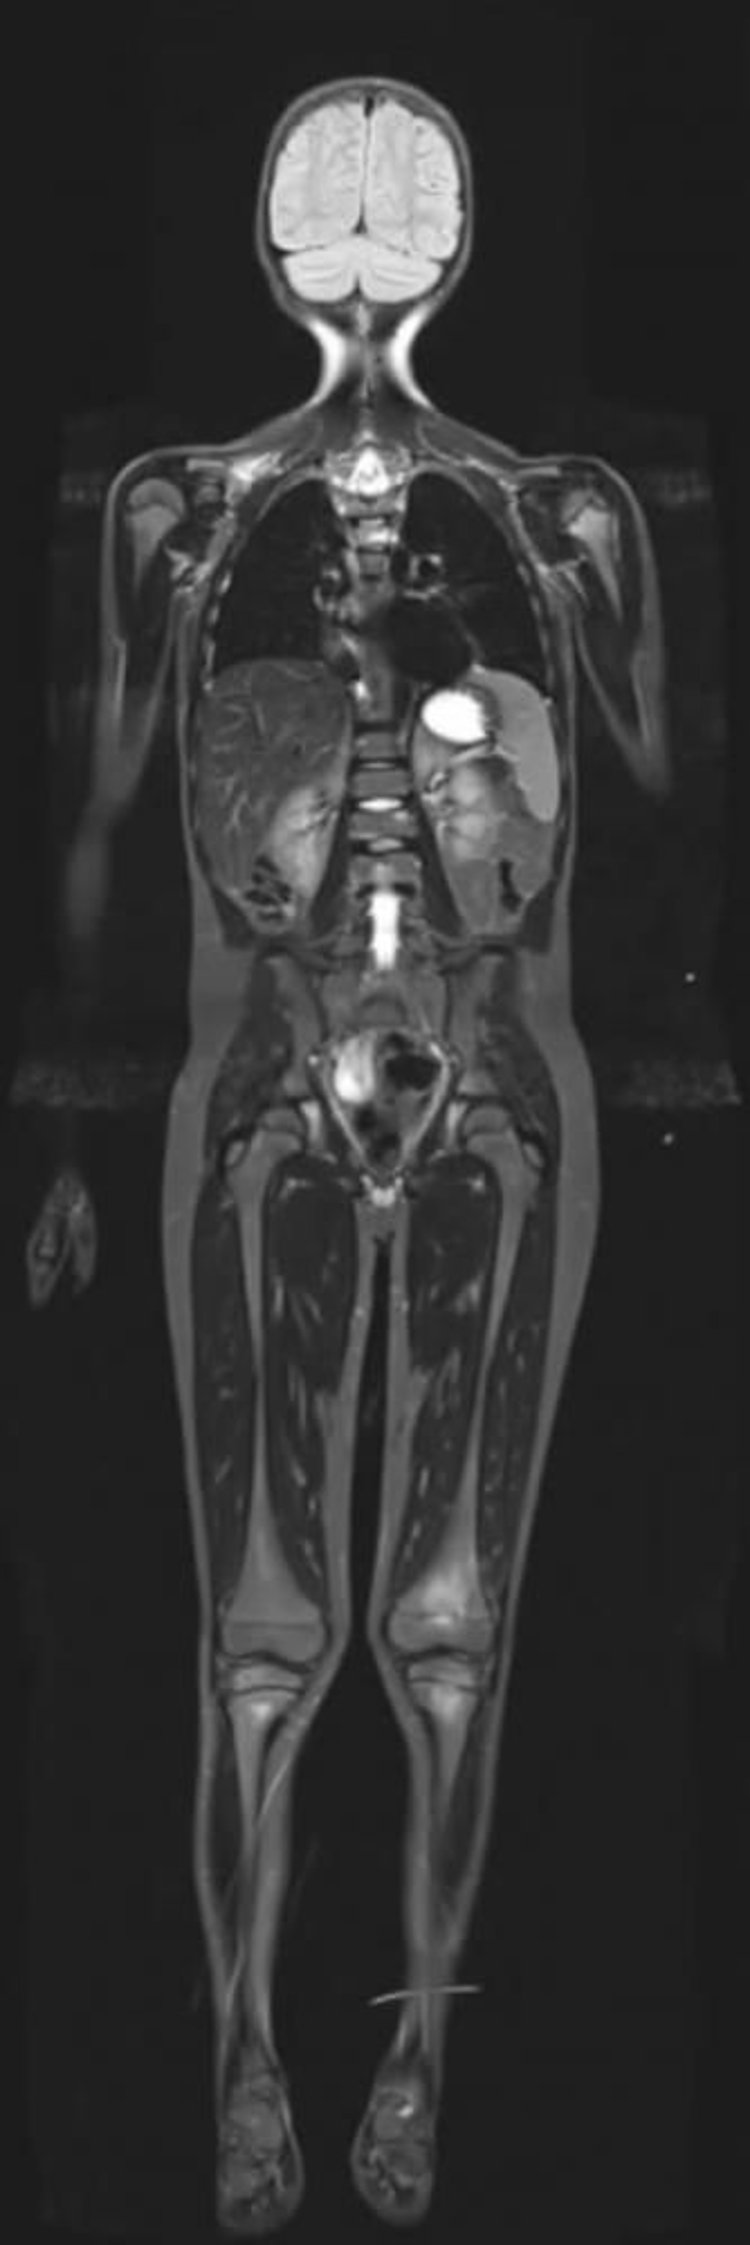

Kurze T1-Inversionswiederherstellung-MRT des gesamten Körpers

Die MRT mit kurzer T1-Inversionserholung kann Signale von Fett unterdrücken und so andere Gewebe mit hohem Wassergehalt hervorheben.

Image courtesy of Hakan Ilaslan, MD.